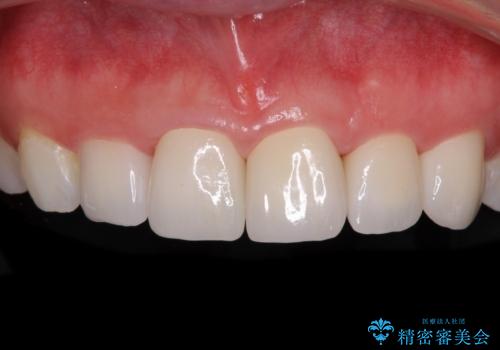

矯正治療にて歯並びを整えた後に、虫歯の大きかった5本の歯をセラミッククラウンにて補綴し、明るい口元になりました。